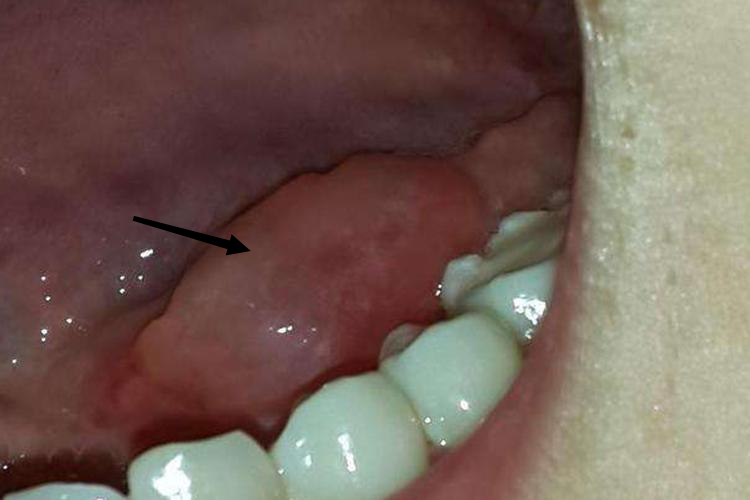

舌下腺囊肿可出现舌下腺一侧肿大症状,表现为舌下一侧有囊肿形成,质地柔软,触之有波动感,多无疼痛感,囊肿破裂时会流出黏稠而略带黄色的蛋清样液体,囊肿暂时消失,数日后又肿大如前。